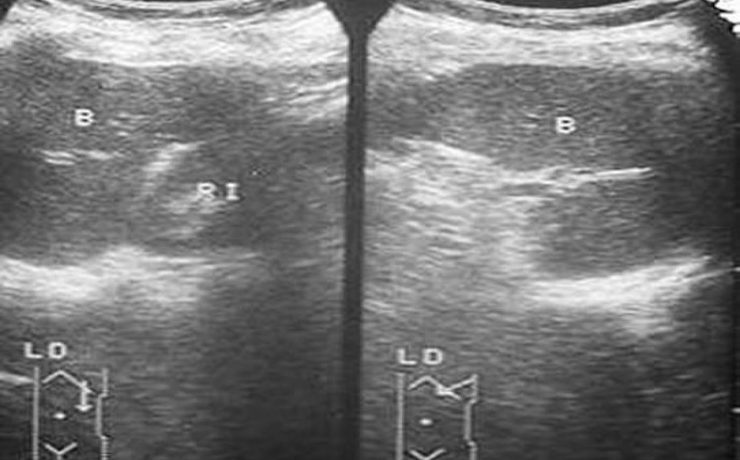

Ultrasonografía en diagnóstico de pancreatitis crónica.

Ultrasonografía en el diagnóstico de pancreatitis crónica El curso y el resultado de las enfermedades pancreáticas suelen ser pobres para la mayoría de los pacientes. Los avances en la formación de imágenes del páncreas son fundamentales para la detección temprana de estas enfermedades. La ecografía ha evolucionado como una herramienta